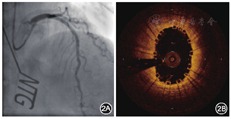

2015年5月11日行冠状动脉造影检查,结果显示:左主干正常;左前降支近段狭窄程度为95%,中远段狭窄程度为30%,血流心肌梗死溶栓试验(thrombolysis in myocardial infarction,TIMI)分级为2~3级;左回旋支远段狭窄程度为70%;右冠状动脉近远段狭窄程度为20%~30%,血流TIMI分级为3级(图1A)。因左前降支近段病变严重,先行球囊预扩张,然后行光学相干断层成像(optical coherence tomography,OCT)检查。OCT结果示最小管腔面积为2.57 mm2,斑块负荷为85.3%(图1B)。以非顺应性高压球囊再次预扩张后,经导丝推送3.5 mm×24 mm NeoVas生物可吸收支架[乐普(北京)医疗器械公司]至左前降支近段病变处,以12 atm(1 atm=101.325 kPa)释放支架。以非顺应性高压球囊后扩张进行支架内整形后,再次行冠状动脉造影和OCT检查(图2)。OCT检查结果示支架扩张满意,贴壁良好,平均管腔面积为7.15 mm2,最小管腔面积为5.85 mm2,斑块负荷为18.6%。术后规律口服阿司匹林肠溶片100 mg(每天1次),替格瑞洛片90 mg(每天2次),阿托伐他汀钙片20 mg(每晚1次)。